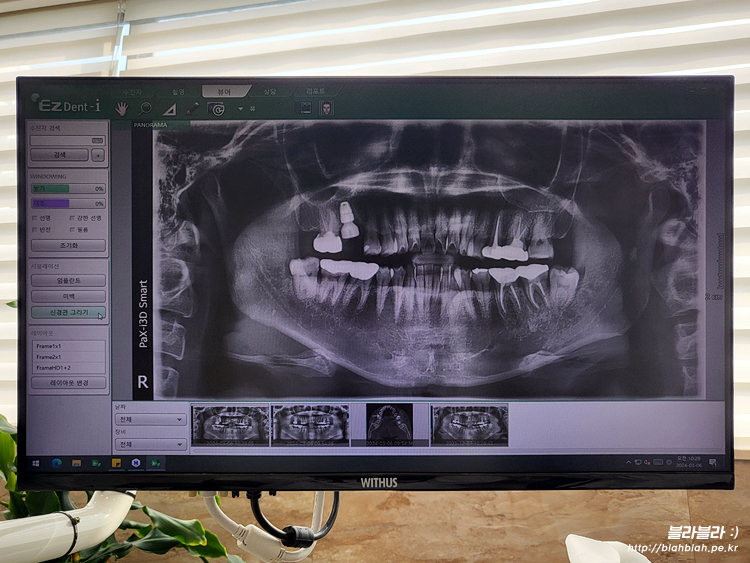

새로 방문한 치과에서 파노라마 사진 찍고

치주과 원장님과 만났습니다.

보시자마자 치아상태가 별로 좋지않고

제가 봐달라고 말씀드린 2군데 모두 임플란트행 ㅠ_ㅜ

임플란트 동의서 작성하고 파노라마 CT 촬영 후

마지막으로 다시 파노라마 촬영하고